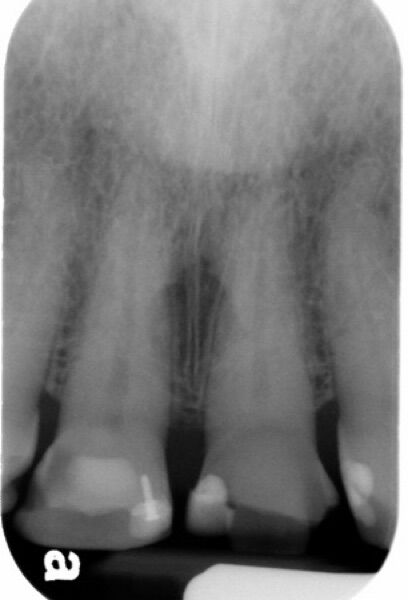

65.在正常人的牙根尖片中,可以看到在兩側正門齒的根部上端近前鼻棘兩側有radiolucent近似卵圓孔狀的影像,可能是:

Incisive foramen